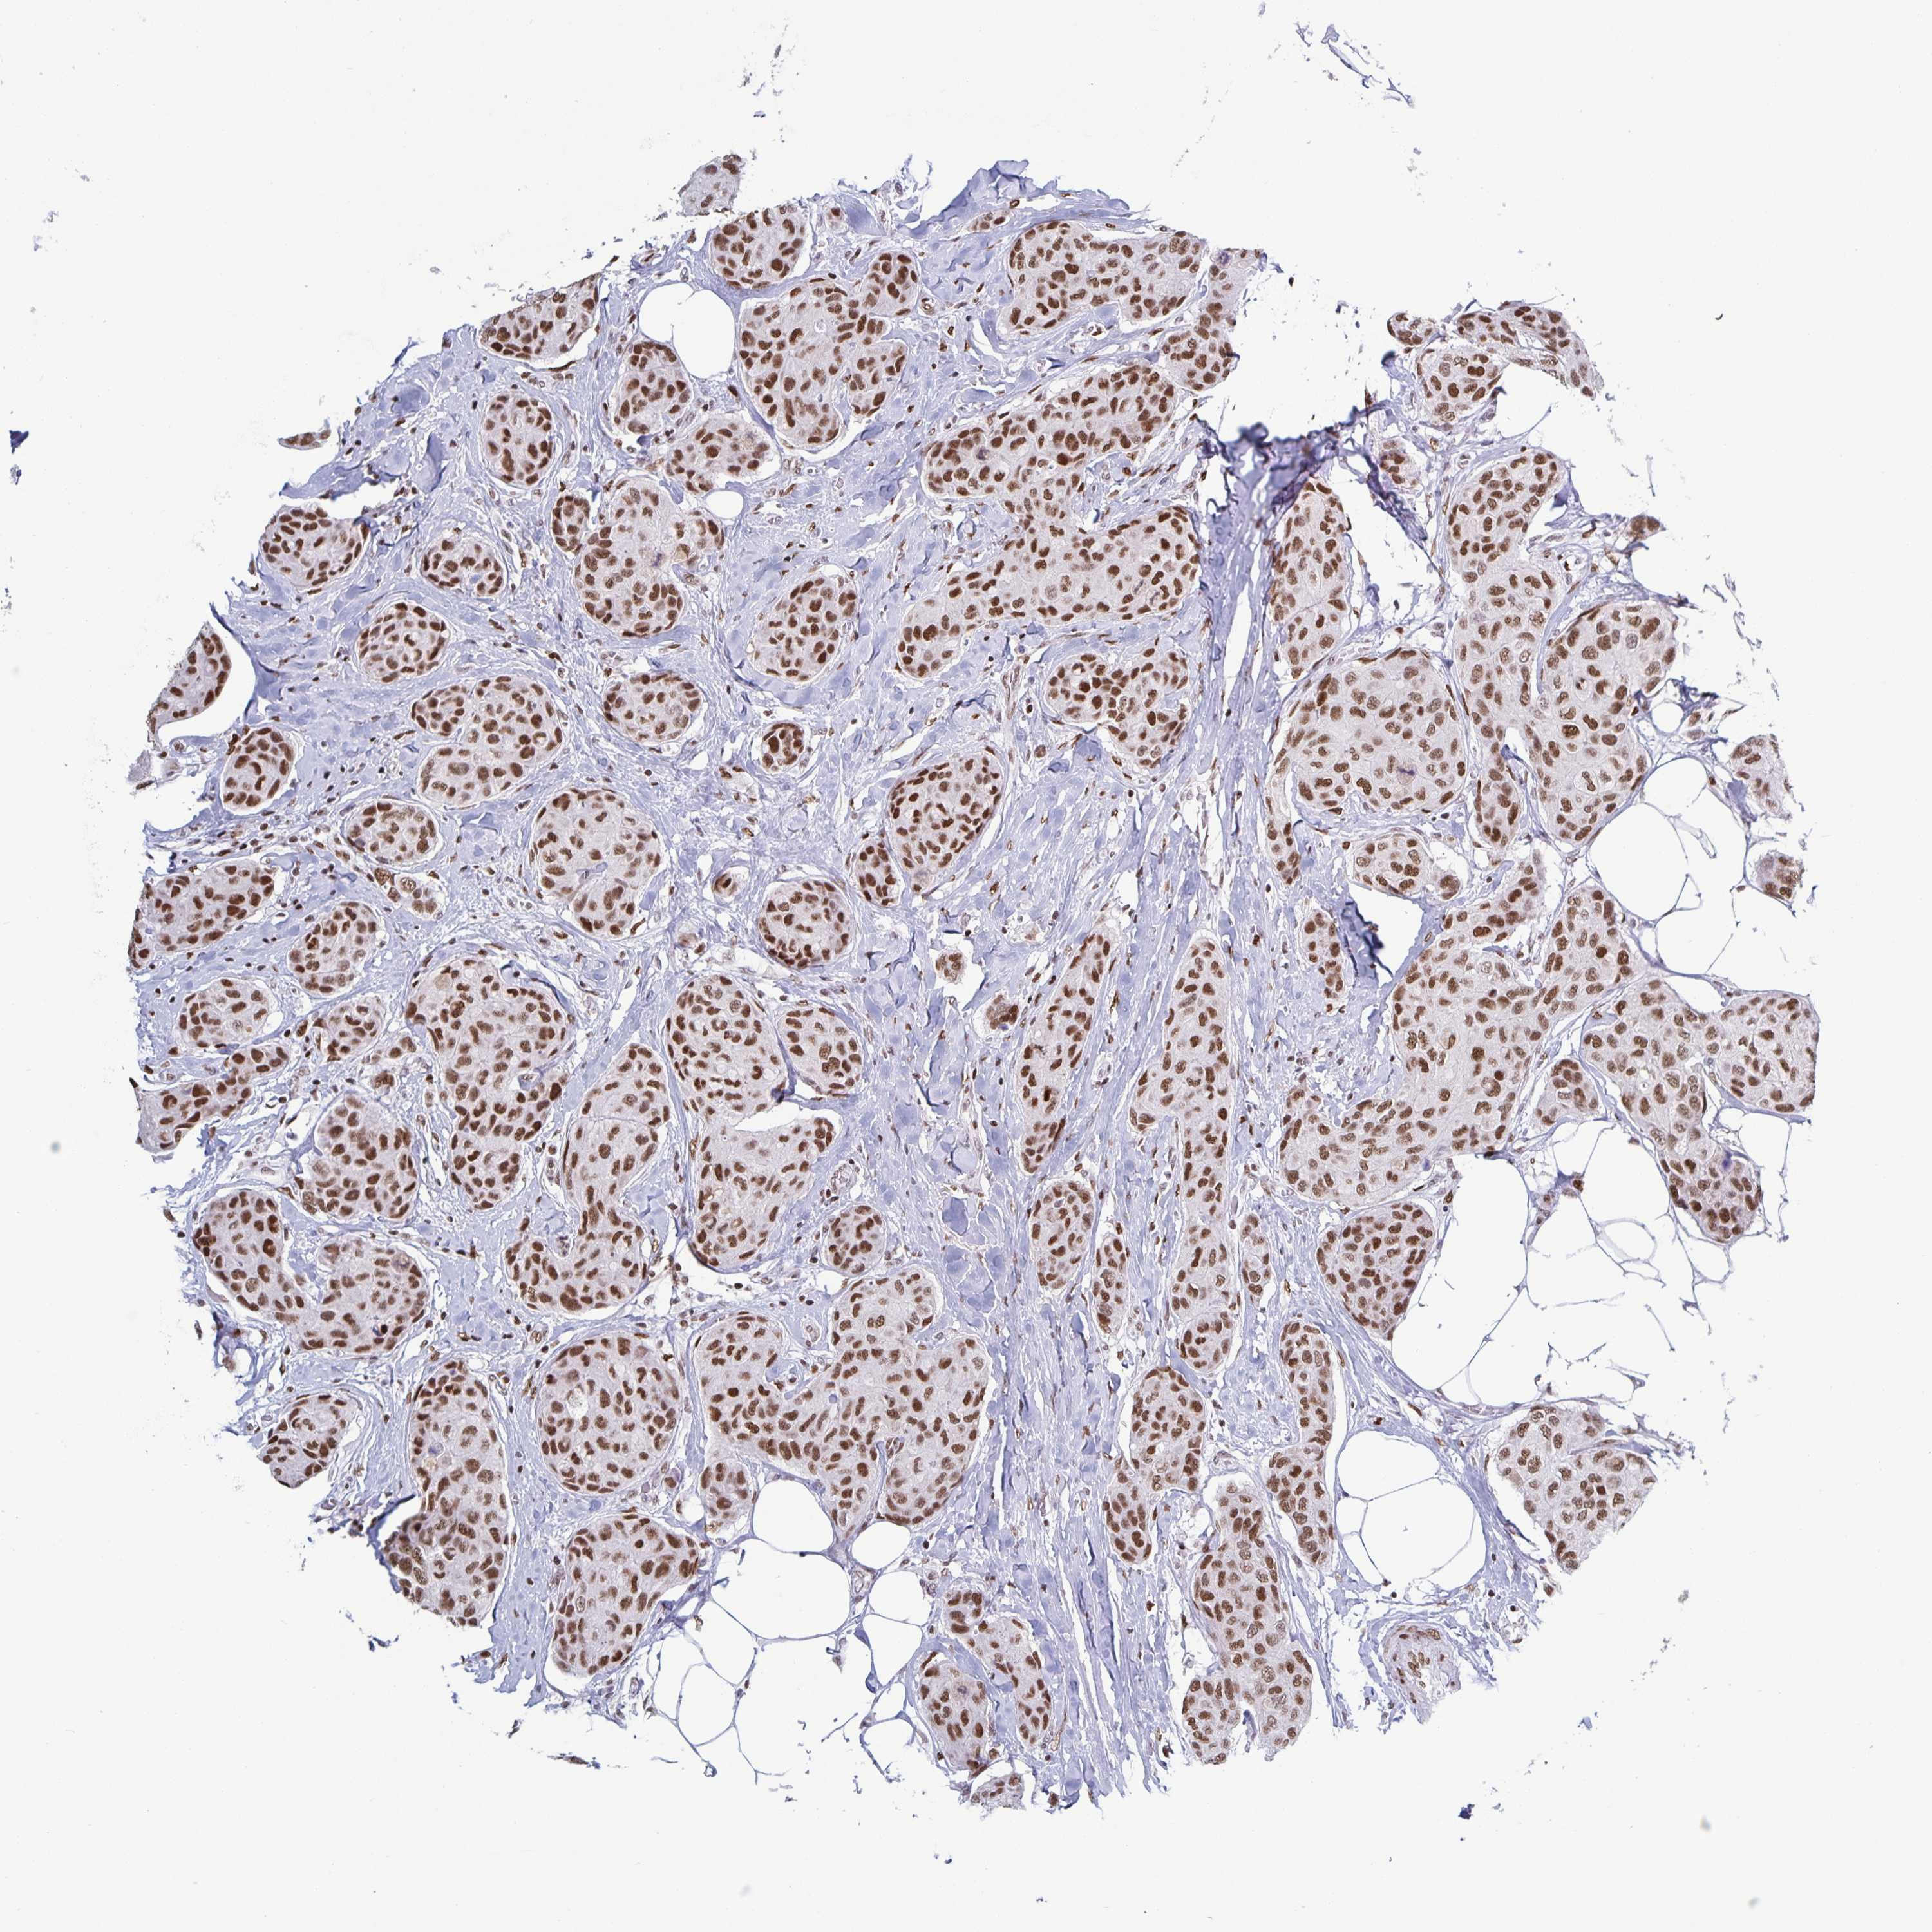

BRCA TCGA BRCA VALIDATION PROTEIN EXPRESSION